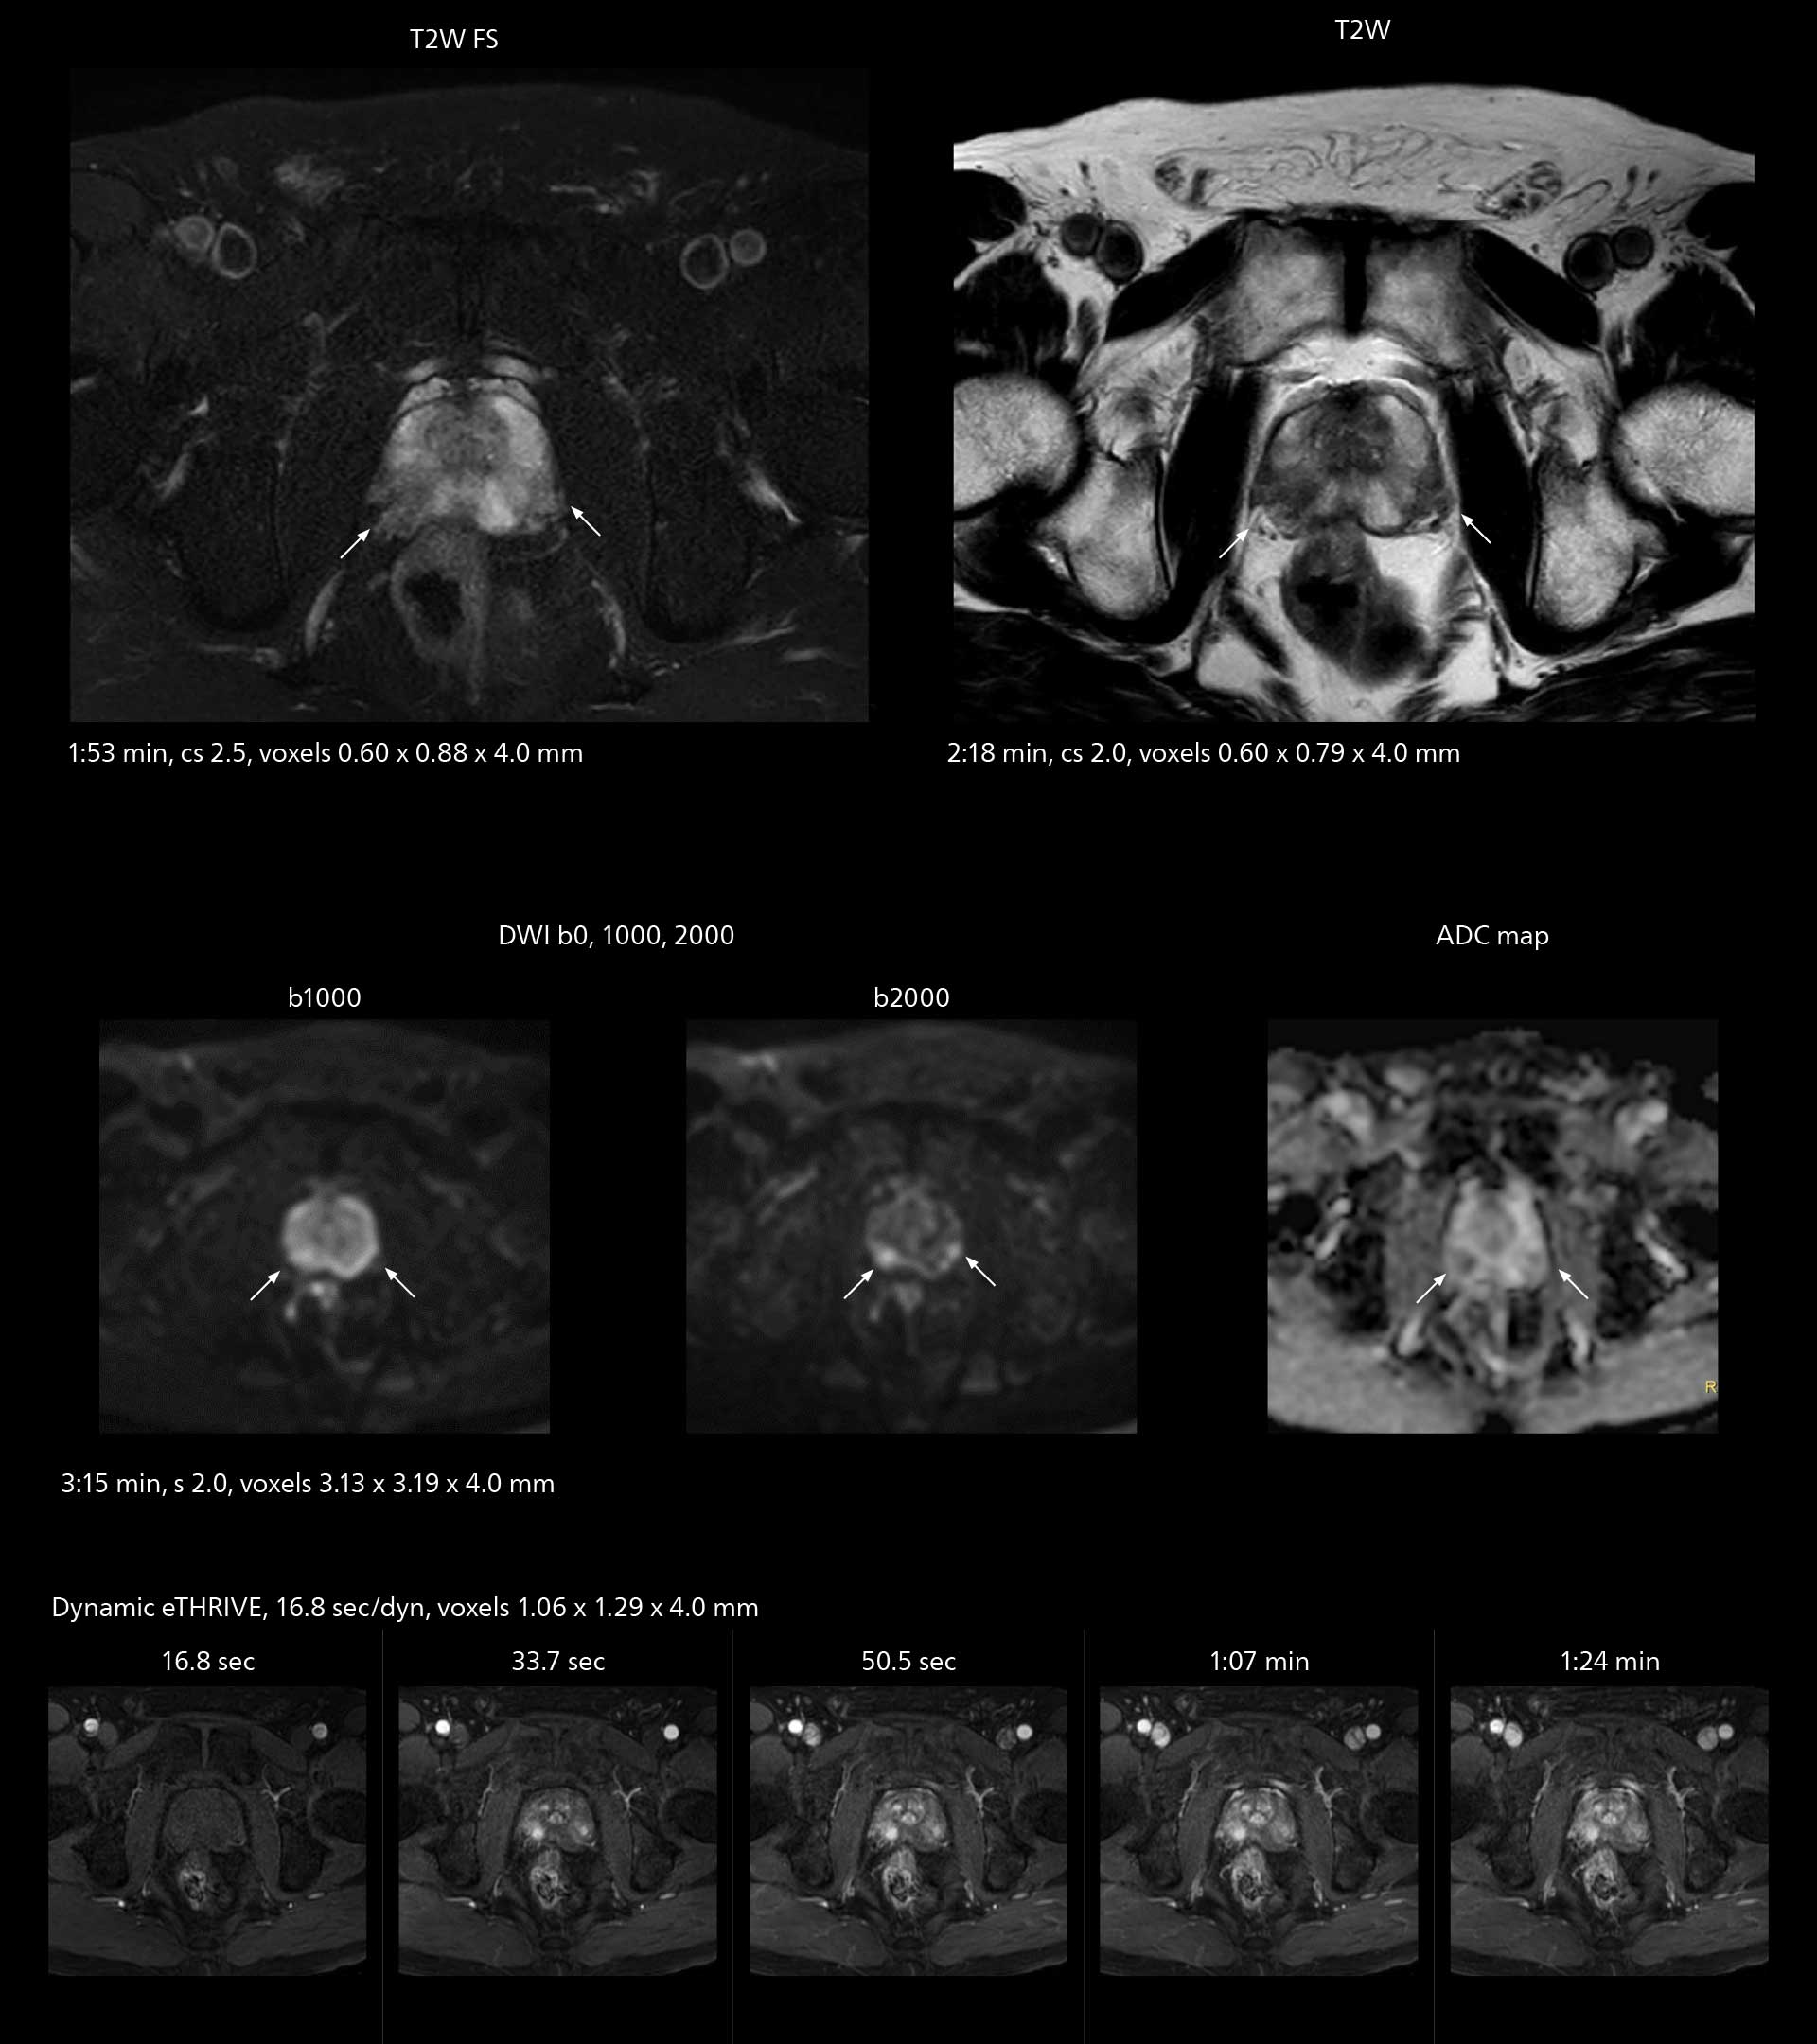

MRI of prostate

Examples of prostate imaging showing faster scan times and improved resolution illustrate the power of SmartPath to Elition X in this case of prostate cancer with PI-RADS score 4.